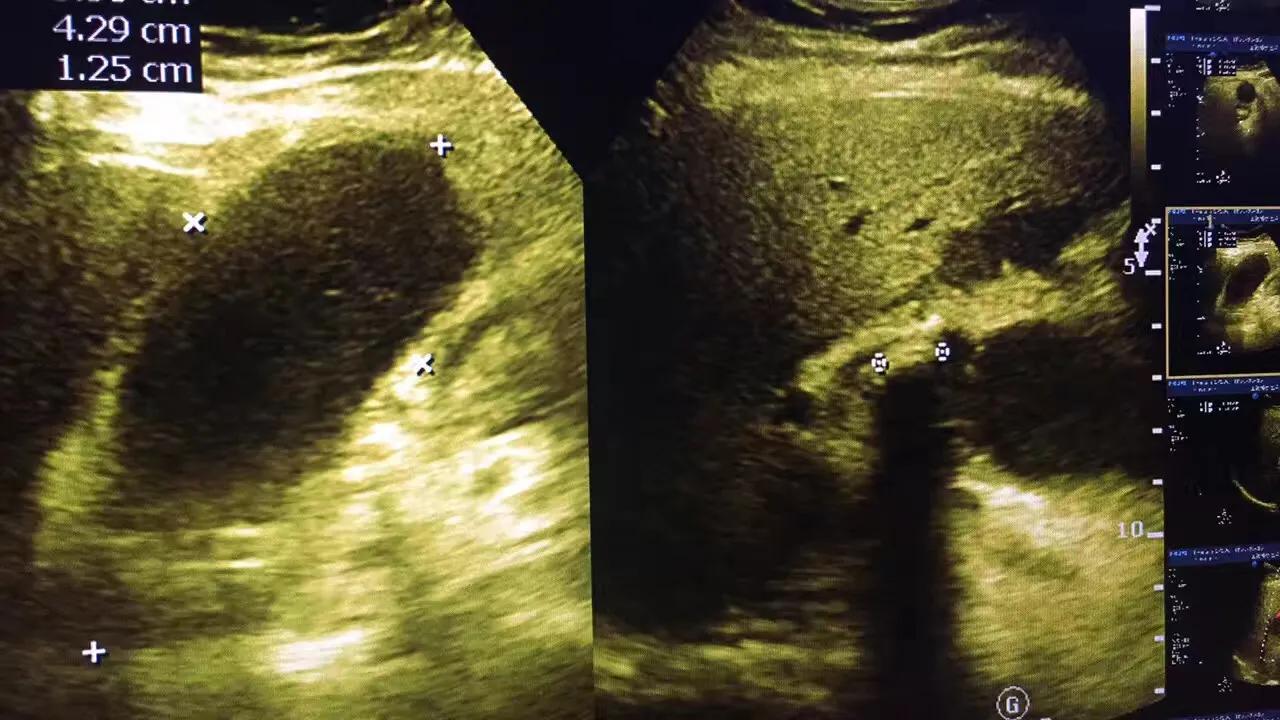

病例2.患者女性,63岁,胆囊颈部结石嵌顿继发急性胆囊炎胆囊穿孔!急诊手术证实胆囊穿孔!